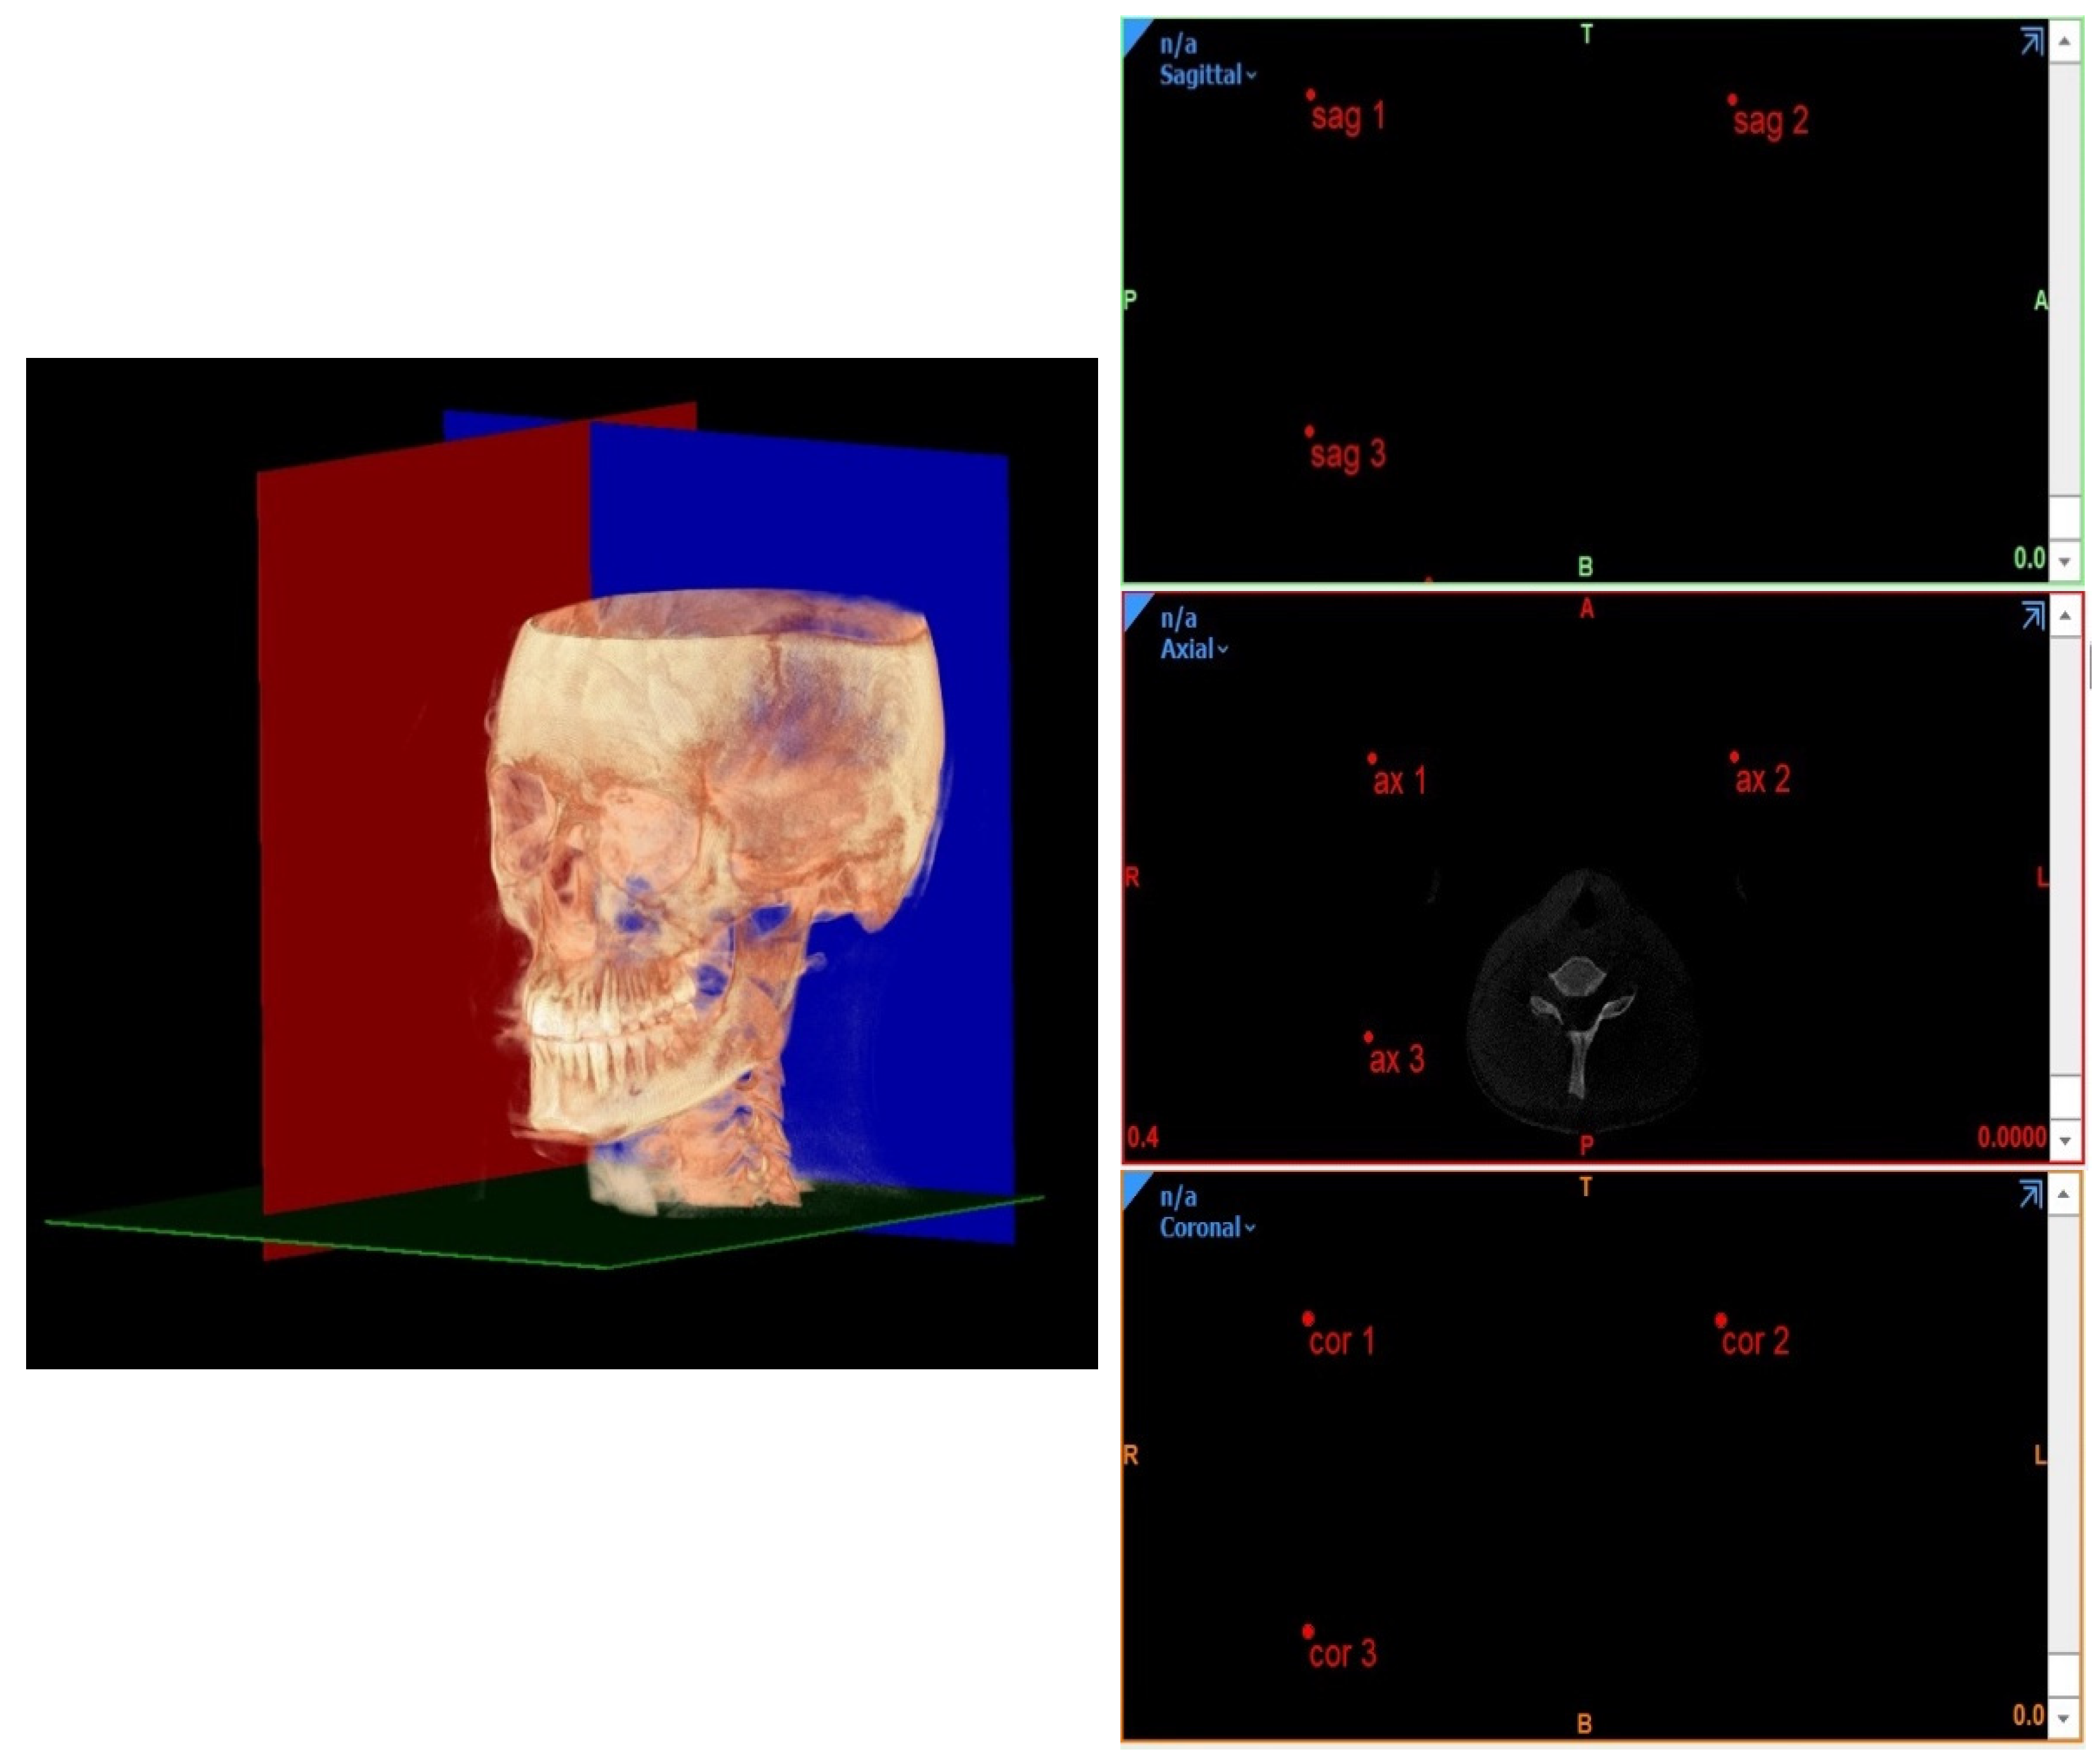

- Planes passing through 3 points;

- Planes passing through 2 points normal to a plane;

- Planes passing through 1 point parallel to a plane.